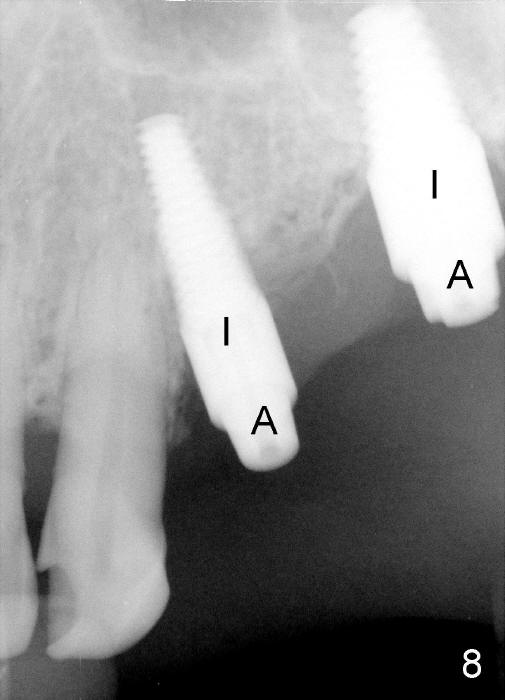

Initially the osteotomy is established with drill/reamers alternated with taps in the septum near the palatal socket. When a 4.5x14 mm tap (Fig.6 T; Fig.7: #14) is inserted, the sinus floor is perforated, but the sinus membrane is intact. When 7x14 mm tap is inserted, the sinus membrane is perforated in the buccal aspect of the osteotomy. The latter is repaired by placement of collagen dressing and then bone graft and membrane again (sandwich). The osteotomy is shifted to the palatal socket by using 5x14 and 6x14 mm taps. When the last tap is removed, the small area of the buccal aspect of the osteotomy is also found to be perforated, but the membrane is intact. When a 6x14 mm implant is placed (Fig.8), the coronal end is close to the middle of the socket (buccopalatally, due to angulation of the palatal socket).

Placement of immediate implant at the site of #12 is relatively easy. Adjustment is more or less mesiodistal. A 2 mm pilot drill (Fig.6 P) is found close to the root of the tooth #11 (red dashed line). The osteotomy is then moved distally (Fig.6 arrow). When 4.5x20 mm tap (Fig.7: #12) and 4.5x17 mm implant (Fig.8 I) are placed, there is distance from the root of the neighboring tooth. Insertion torque of the both implants is >60 Ncm. Abutments are placed (A in Fig.8) for immediate provisional.